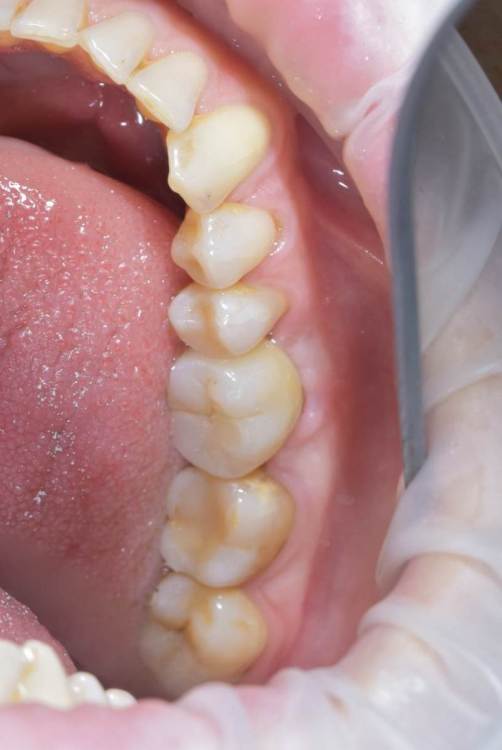

TIGER Опубликовано 22 сентября, 2022 Поделиться Опубликовано 22 сентября, 2022 Всем привет!Давно ничего не закидывал,небольшой клинический случай,банальщина,замещение одиночного моляра,система Straumann понравилась,как всегда только оригинальные компоненты? 8 1 Ссылка на комментарий

TIGER Опубликовано 23 сентября, 2022 Автор Поделиться Опубликовано 23 сентября, 2022 @Aquarius спасибо,я всегда фоткаю с расцветкой и тут мультилэйер циркон 1 Ссылка на комментарий

annda Опубликовано 1 октября, 2022 Поделиться Опубликовано 1 октября, 2022 На фото в аксиальной проекции показалось , что TL стоит:) А на снимке, совсем другой. Надо же, обман зрения. Ссылка на комментарий

TIGER Опубликовано 1 октября, 2022 Автор Поделиться Опубликовано 1 октября, 2022 (изменено) @annda да,вы про лунку?похоже,согласен,шейка широкая там 4.8 диаметр,но если присмотреться на внутренности видно,что это не SynOcta)А конус Изменено 1 октября, 2022 пользователем TIGER 1 Ссылка на комментарий